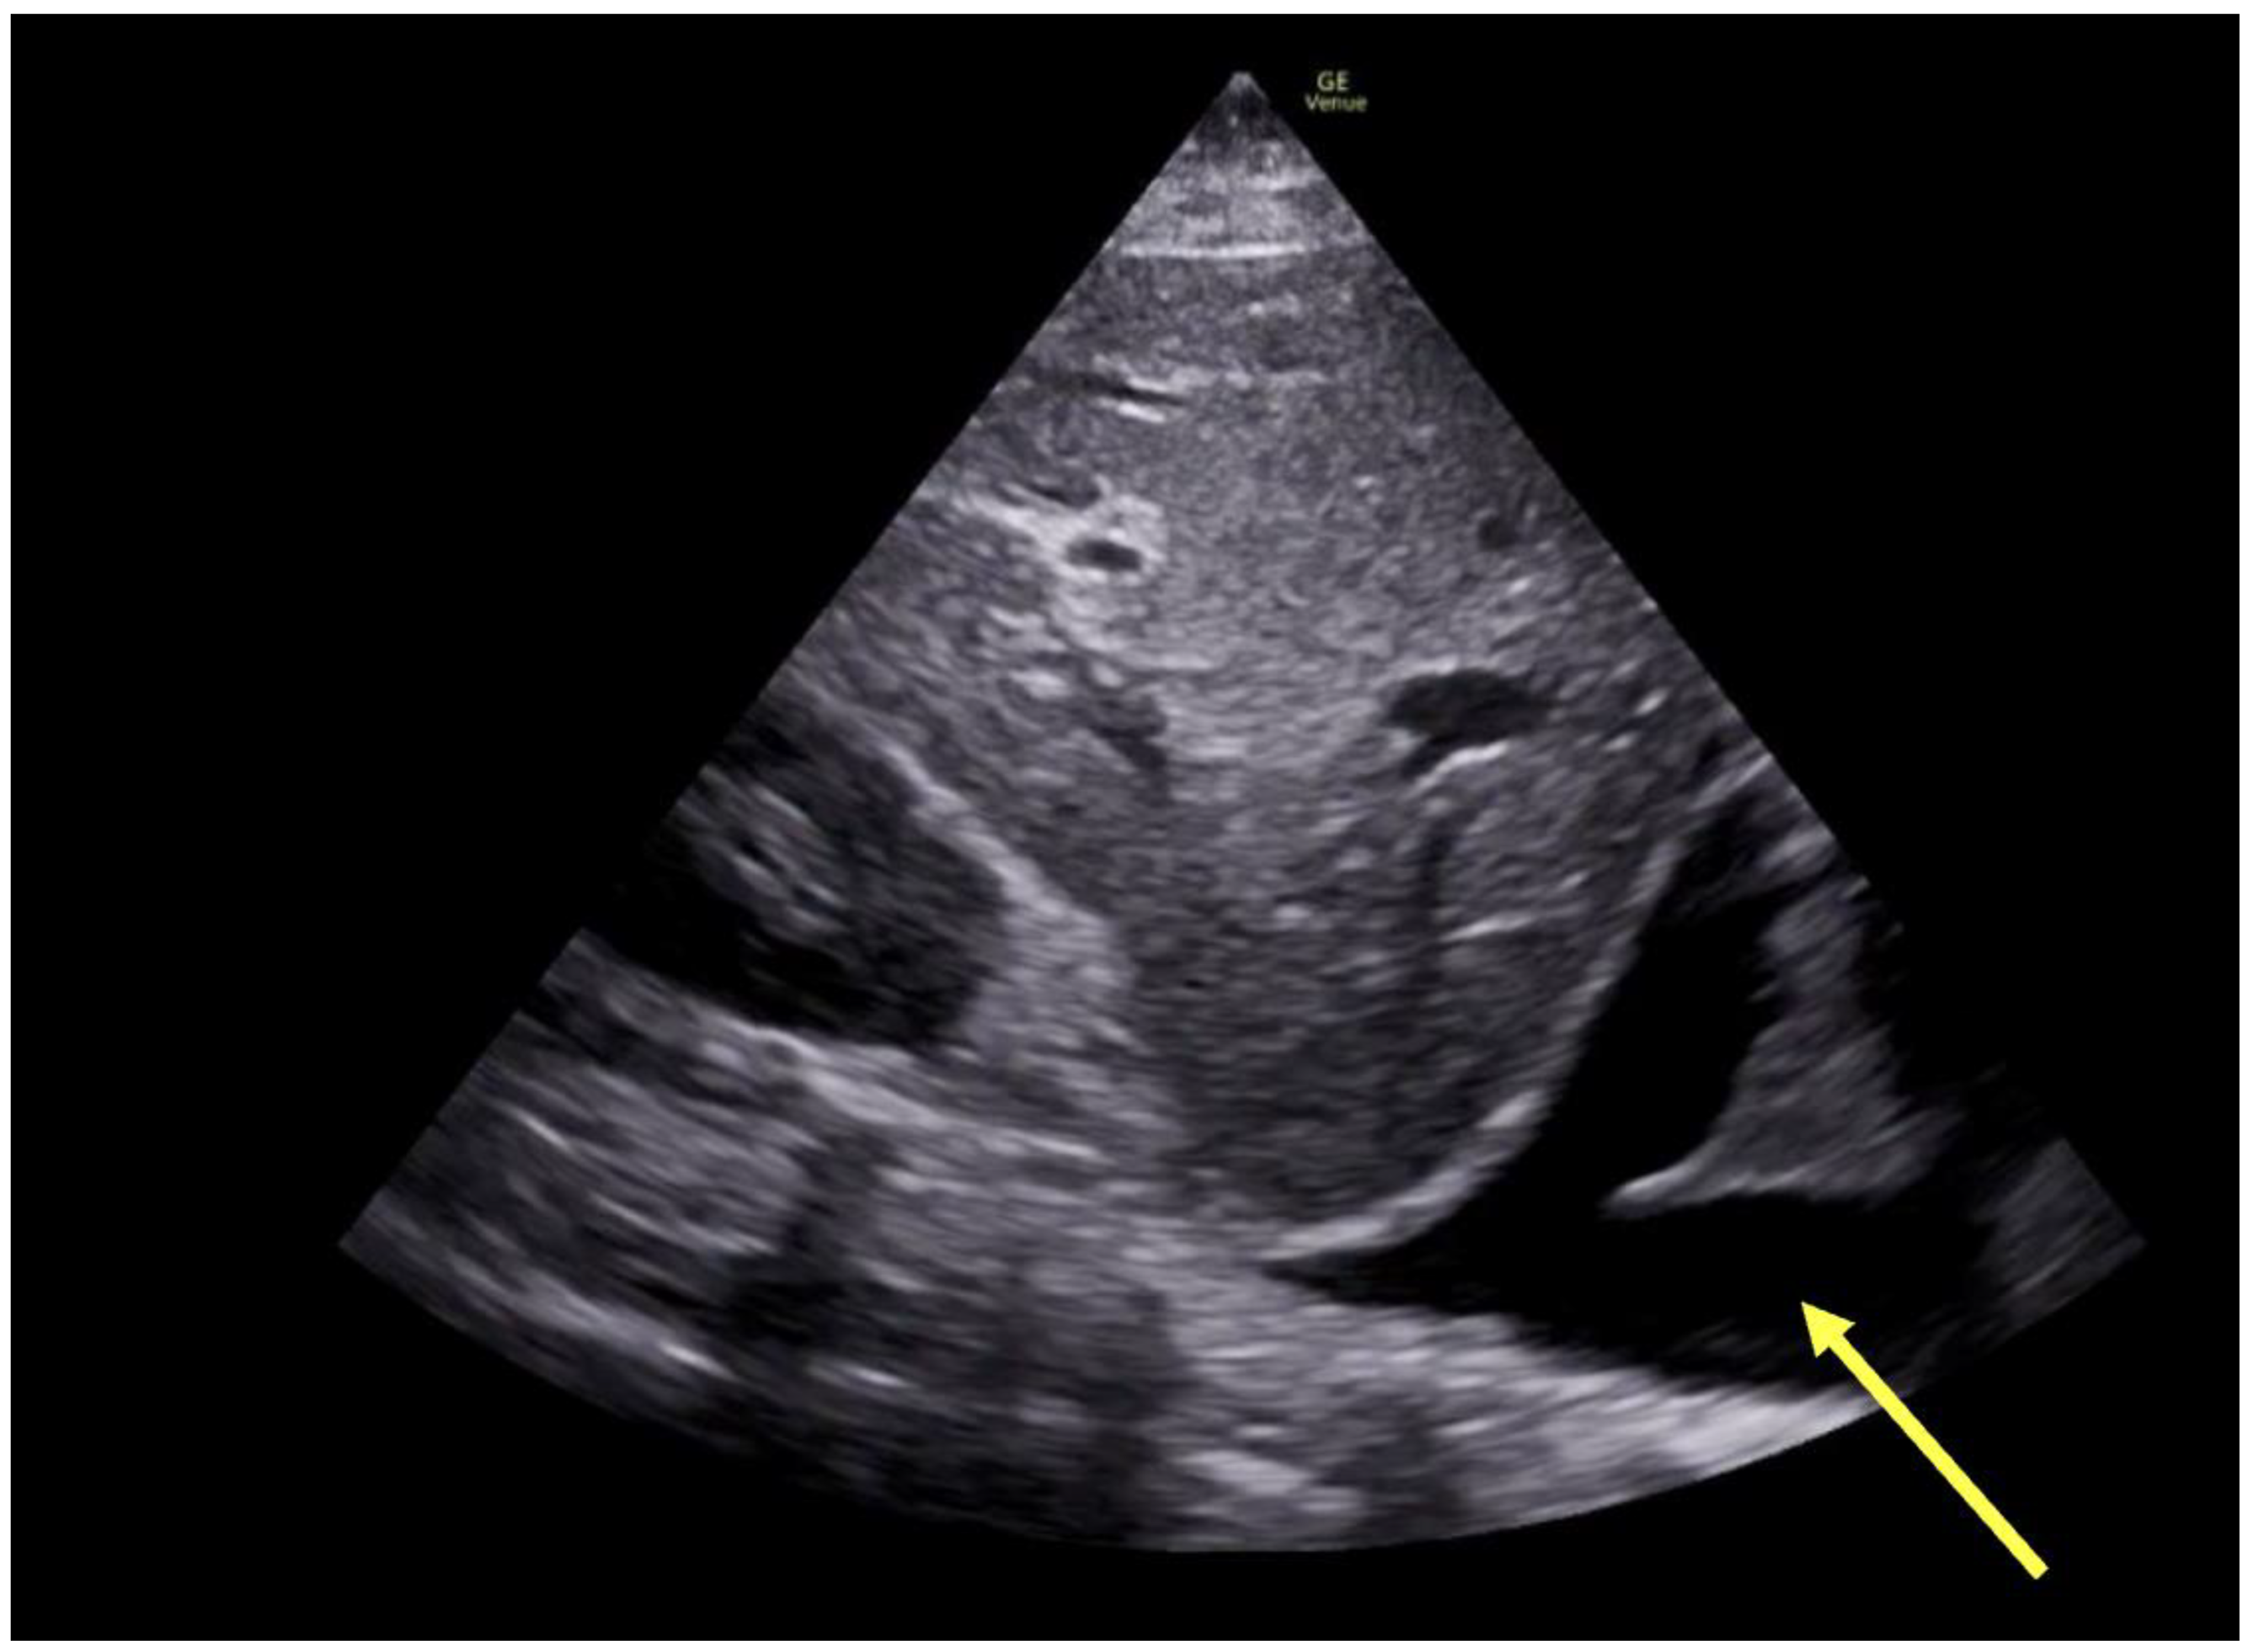

| Assessment of peripheral vasculature for size, disease, thrombus | Assessment for vascular or intracardiac injury (dissection, tamponade) | Assessment of aortic mixing point |

| Assessment of peripheral vasculature for size, disease, thrombus | Assessment of return (outflow) “jet” | Confirmation of cannula position |